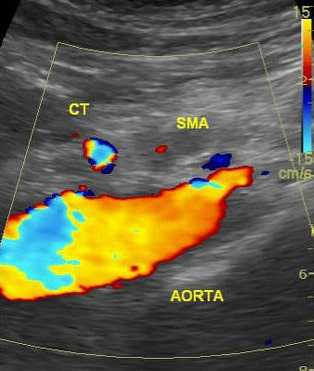

![УЗИ картина закупорки верхней брыжеечной артерии]()

УЗИ брюшной аорты

УЗИ брюшной аорты позволяет выявить тромбоз брыжеечной артерии или чревного ствола. Преимуществом метода является его быстрая доступность и отсутствие осложнений. Брюшная аорта осматривается в продольном и в поперечном срезе в режиме цветового картирования. Определяется скорость кровотока по аорте и ее ветвям. Метод обладает достаточно высокой чувствительностью, но его результаты зависят от опыта врача, проводящего исследование и правильной интерпретации полученных данных.